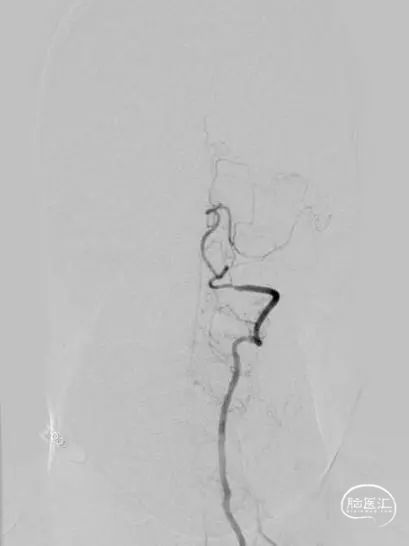

300cm微导丝携Gateway球囊到位,行球囊扩张及预扩张后造影。

小结和体会

1、本例患者反复出现神经功能障碍,血管评估提示双侧椎动脉V4段均为重度狭窄,左侧狭窄位置位于发出小脑后下动脉下方,紧邻小脑后下动脉,同时左侧小脑后下动脉起始段存在有重度狭窄,相对粗大。

2、右侧椎动脉V4段血管狭窄附近未见有明确血管分支,因此手术选择了行右侧椎动脉V4段球囊扩张及支架置入术,因双侧椎动脉V4段狭窄以远椎动脉及基底动脉汇合处血管良好,因此右侧椎动脉V4段狭窄处支架置入术后病人右侧椎动脉及远端基底动脉血流明显改善外,同时也可见到左侧椎动脉V4段逆向显影至左侧小脑后下动脉。同时避免了左侧椎动脉支架置入术中对左侧小脑后下动脉的影响导致小脑后下动脉缺血事件发生的可能。

3、Gateway球囊为半顺应性球囊,推送性能良好,术中缓慢扩张,可减少球囊移位、血管变形及夹层等,为后续支架置入提供了良好的条件。

4、EZ支架通过性好,释放顺畅,径向支撑力强,支架贴壁良好。